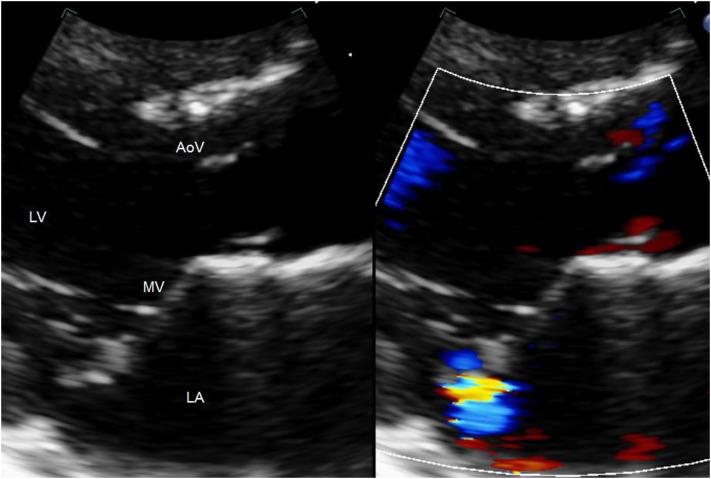

Mitral valve prolapse is prevalent in about 6% of young healthy females yet two to three times as prevalent in patients with hyperthyroidism [1, 8]. Hyperthyroidism is often missed as an underlying diagnosis when mitral valve prolapse is visualized by echocardiogram. There are many cardiac findings reported in the literature associated with hyperthyroidism. However, hyperthyroidism may be difficult to diagnose in the early stages of the disease process without other classic signs and symptoms. We report a case of an adolescent female who presented to our cardiology clinic with palpitations and chest pain diagnosed with hyperthyroidism after subtle findings of mitral valve prolapse and trivial mitral regurgitation. This case report will review the classic cardiac changes which may be observed on echocardiography in patients with hyperthyroidism.

二尖瓣脱垂在约6%的年轻健康女性中普遍存在,但在甲状腺功能亢进患者中的发生率是前者的两到三倍[1, 8]。当通过超声心动图发现二尖瓣脱垂时,甲状腺功能亢进常被漏诊为潜在病因。文献中报道了许多与甲状腺功能亢进相关的心脏表现。然而,在疾病早期,如果没有其他典型的体征和症状,甲状腺功能亢进可能难以诊断。我们报告一例青少年女性,因心悸和胸痛就诊于我们的心脏病诊所,在发现轻微的二尖瓣脱垂和轻度二尖瓣反流后被诊断为甲状腺功能亢进。本病例报告将回顾甲状腺功能亢进患者超声心动图上可能观察到的典型心脏变化。